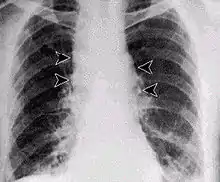

Inhalation anthrax usually develops within a week after exposure, but may take up to 2 months. During the first few days of illness, most people have fever, chills, and fatigue. These symptoms may be accompanied by cough, shortness of breath, chest pain, and nausea or vomiting, making inhalation anthrax difficult to distinguish from influenza and community-acquired pneumonia. This is often described as the prodromal period.[20]

Over the next day or so, shortness of breath, cough, and chest pain become more common, and complaints not involving the chest such as nausea, vomiting, altered mental status, sweats, and headache develop in one-third or more of people. Upper respiratory tract symptoms occur in only a quarter of people, and muscle pains are rare. Altered mental status or shortness of breath generally brings people to healthcare and marks the fulminant phase of illness.

It infects the lymph nodes in the chest first, rather than the lungs themselves, a condition called hemorrhagic mediastinitis, causing bloody fluid to accumulate in the chest cavity, therefore causing shortness of breath. The second (pneumonia) stage occurs when the infection spreads from the lymph nodes to the lungs. Symptoms of the second stage develop suddenly within hours or days after the first stage. Symptoms include high fever, extreme shortness of breath, shock, and rapid death within 48 hours in fatal cases.[21]

The infection of herbivores (and occasionally humans) by the inhalational route normally begins with inhaled spores being transported through the air passages into the tiny air sacs (alveoli) in the lungs. The spores are then picked up by scavenger cells (macrophages) in the lungs and are transported through small vessels (lymphatics) to the lymph nodes in the central chest cavity (mediastinum). Damage caused by the anthrax spores and bacilli to the central chest cavity can cause chest pain and difficulty breathing. Once in the lymph nodes, the spores germinate into active bacilli that multiply and eventually burst the macrophages, releasing many more bacilli into the bloodstream to be transferred to the entire body. Once in the blood stream, these bacilli release three proteins named lethal factor, edema factor, and protective antigen. The three are not toxic by themselves, but their combination is incredibly lethal to humans.[25] Protective antigen combines with these other two factors to form lethal toxin and edema toxin, respectively. These toxins are the primary agents of tissue destruction, bleeding, and death of the host. If antibiotics are administered too late, even if the antibiotics eradicate the bacteria, some hosts still die of toxemia because the toxins produced by the bacilli remain in their systems at lethal dose levels.